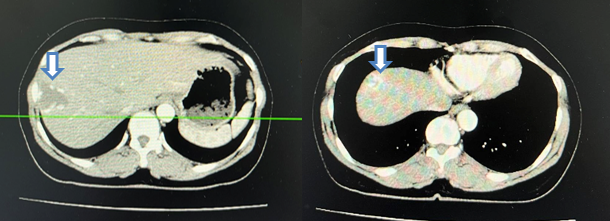

- Cộng hưởng từ tiểu khung:

Hình 3: Chụp cộng hưởng từ ổ bụng, tập trung tiểu khung (13/06/22): Hình ảnh u bàng quang T2aNxMx, vị trí 7h có nốt kích thước 12x16mm (mũi tên đỏ), trong lòng có hình ảnh sonde tiểu (mũi tên xanh), không có sỏi